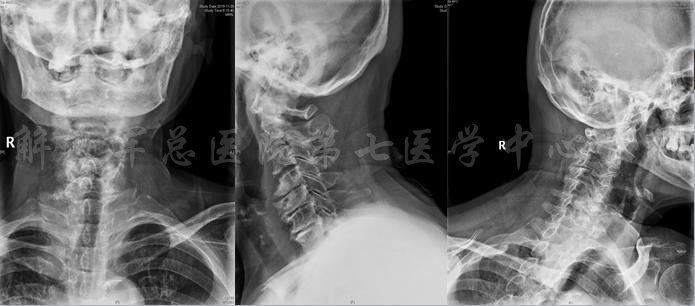

X线片

颈部X线片

X线片:TL cobb 38、PI 53、SS 13、PT 40、LL 9